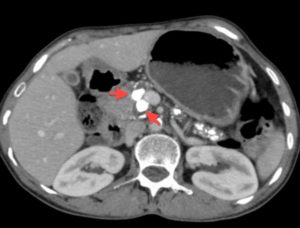

На представленной ниже фотографии отображена рентгенограмма (фото А) и томограмма брюшной полости больного, страдающего хроническим кальцифирующим панкреатитом, поступившим в хирургическое отделение после 72 часов острого болевого синдрома в эпигастральной области, с тошнотой и рвотой. Лабораторные исследования показали повышенный уровень в сыворотке крови липазы (173 U на литр), что указывает на диагноз панкреатит. Больной не употребляет алкоголь, а предыдущими исследованиями других причин развития панкреатита установлено не было.

Стрелками на рентгенограмме и на изображении, полученном при компьютерной томографии, указаны плотные кальцифицированные образования в поджелудочной железе.

Клиническая картина свидетельствует об обструкции главного панкреатического протока камнями, что типично для хронического кальцифицирующего панкреатита.